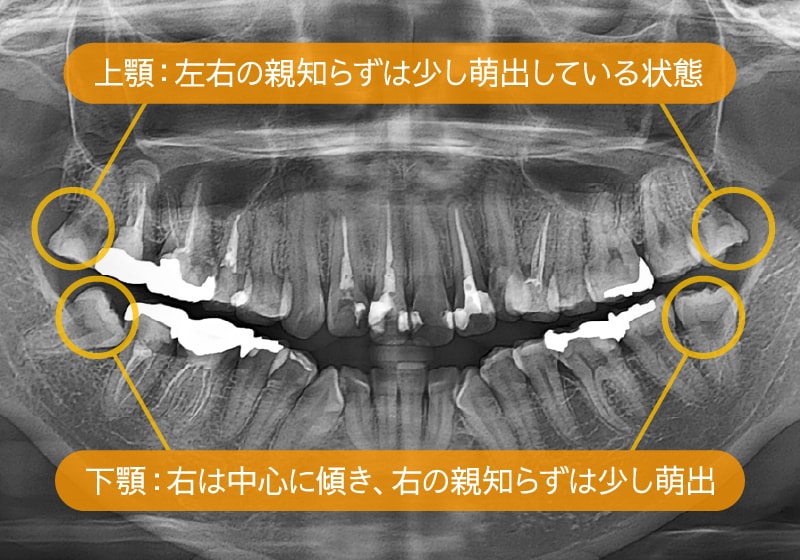

4本抜歯後、右上下の親知らずが萌出し活用した症例

治療開始時:パノラマ

抜歯後:パノラマ